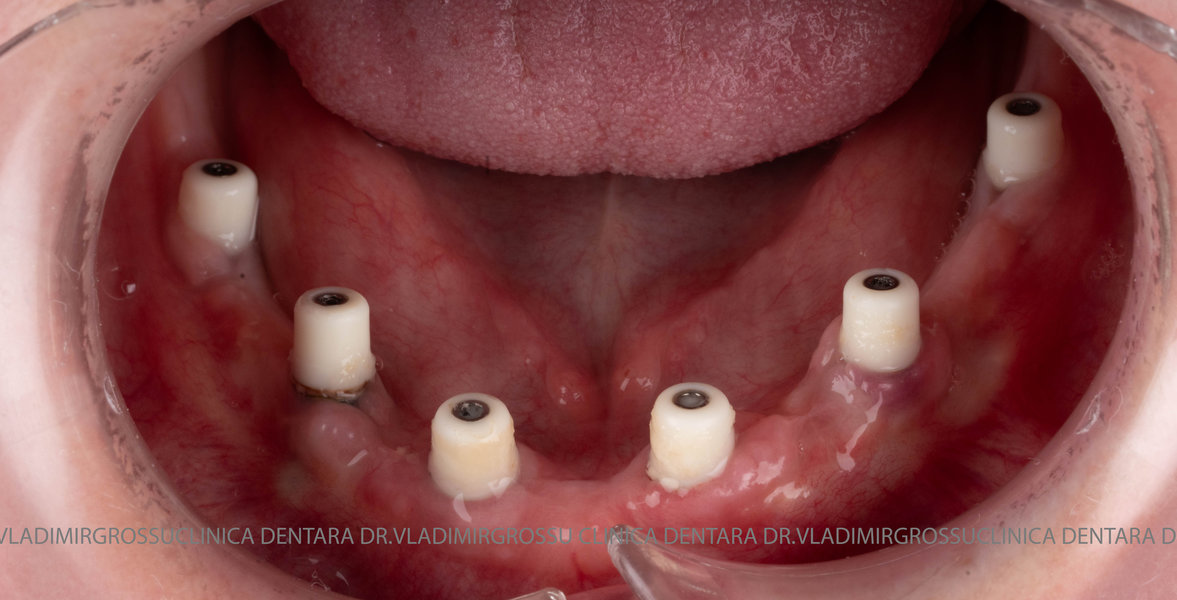

Cazuri clinice conceptul All-on-6